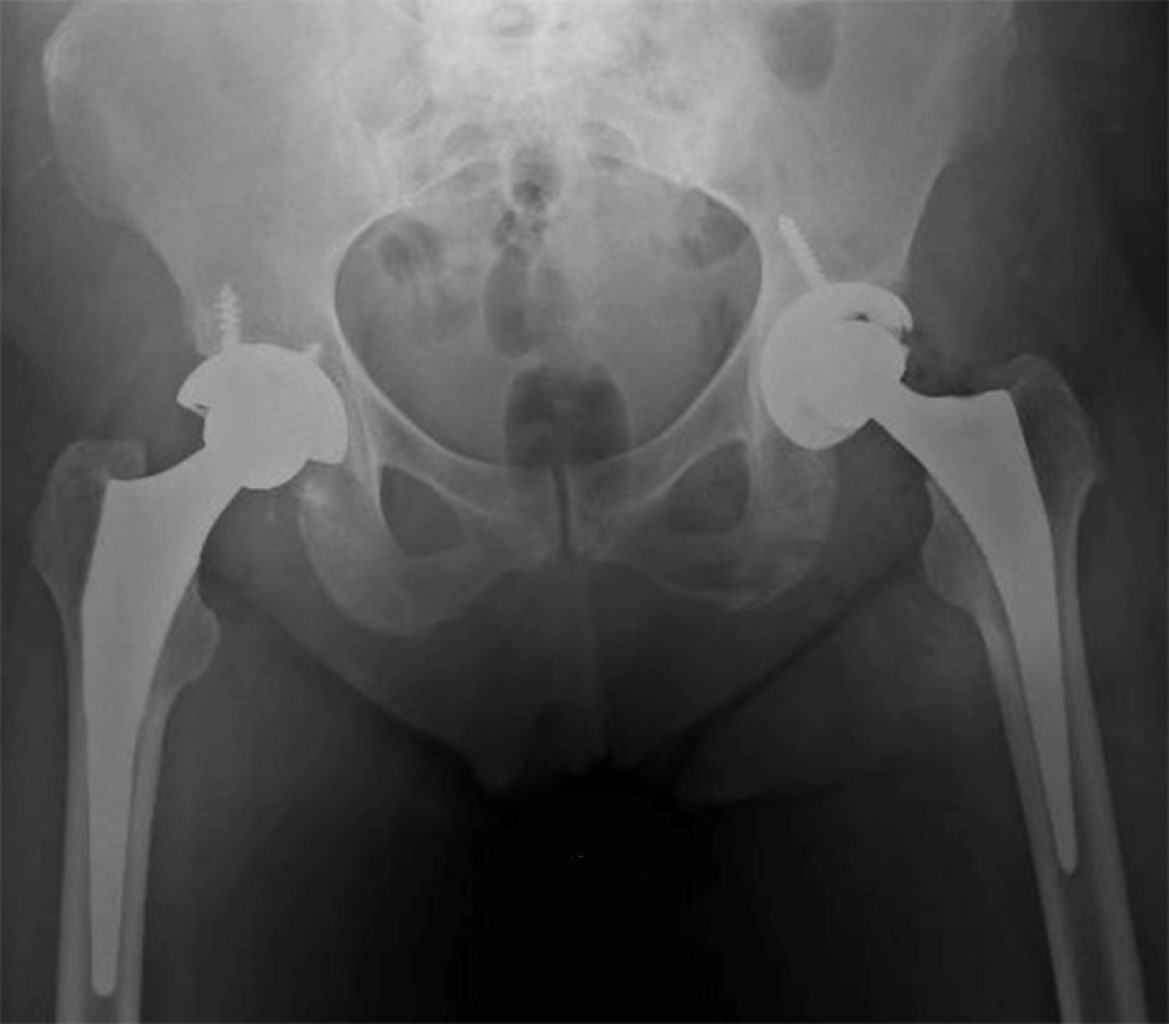

Alkaptonuria: evolution and course of the disease towards ochronotic arthropathy. Series of cases managed with joint replacement

Introduction: alkaptonuria is a very rare metabolic disease with autosomal recessive inheritance due to HGA oxidase deficiency. Classically described and diagnosed in the third to fourth decade of life, affecting both men and women; Its diagnostic impression is clinical based on the blue/black coloration of the conjunctivae, however it is confirmed by the specific analysis of the enzyme in the urine, to date there is no cure and its treatment is palliative and symptomatic. Material and methods: descriptive, observational, case series study, the primary objective of which is to describe the progression of the disease and its involvement in the musculoskeletal system. Results: two clinical cases are presented in women and men in which the broad clinic is illustrated, its progressive advance and the different alterations that it can generate in the musculoskeletal system. Conclusions: alkaptonuria is a rare disease which leads to a severe secondary arthropathy, currently without a specific management which is based on treating the symptoms, in its final stages joint replacements are a management option with satisfactory results for the relief of pain.

Figure 2